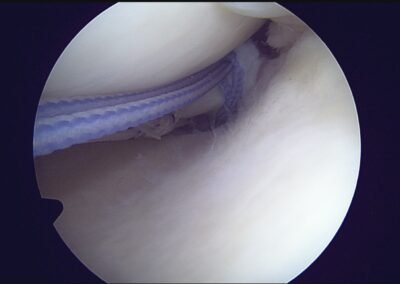

GalleryShoulder rotator cuff repair Meniscus root repair Meniscus repair Bankart repair for recurrent shoulder dislocation ACL reconstruction Machines Instruments